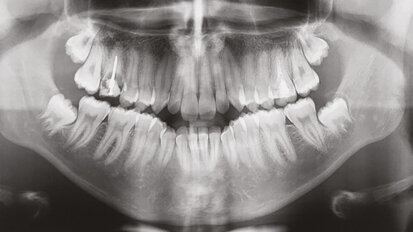

Navigovaný endodontický přístup u kalcifikovaných frontálních zubů: Kazuistika

Obliterace pulpy kanálku (Pulp Canal Obliteration – PCO) nebo kalcifikující metamorfóza je některými autory považována za odpověď pulpy na ...

3D technologie v diagnostice a léčbě endodontických onemocnění

Technologie spjatá s endodontickou terapií prošla v posledních letech opravdovou revolucí. Po dlouhá léta byly využívány jako základ pro ...